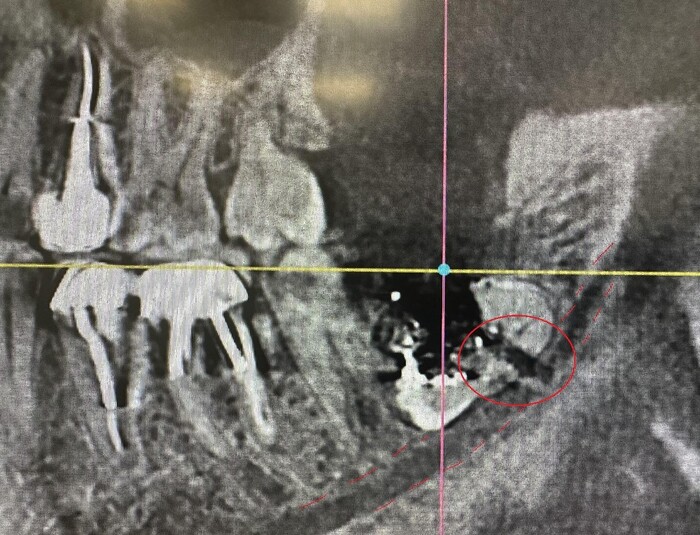

Ниже фрагмент компьютерной томографии, а интересующий имплантат справа снизу:

Увы, но рядом стоящий 7й зуб треснул пополам и было принято решение о его удалении и установке имплантата.